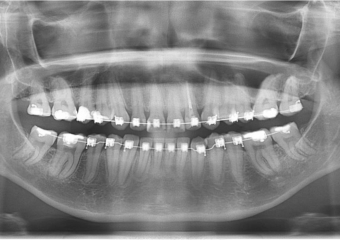

Raio x inicial

Raio x final